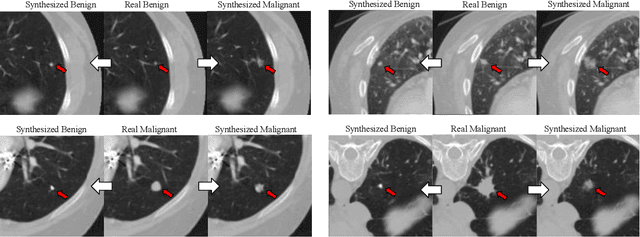

Abstract:Though large-scale datasets are essential for training deep learning systems, it is expensive to scale up the collection of medical imaging datasets. Synthesizing the objects of interests, such as lung nodules, in medical images based on the distribution of annotated datasets can be helpful for improving the supervised learning tasks, especially when the datasets are limited by size and class balance. In this paper, we propose the class-aware adversarial synthesis framework to synthesize lung nodules in CT images. The framework is built with a coarse-to-fine patch in-painter (generator) and two class-aware discriminators. By conditioning on the random latent variables and the target nodule labels, the trained networks are able to generate diverse nodules given the same context. By evaluating on the public LIDC-IDRI dataset, we demonstrate an example application of the proposed framework for improving the accuracy of the lung nodule malignancy estimation as a binary classification problem, which is important in the lung screening scenario. We show that combining the real image patches and the synthetic lung nodules in the training set can improve the mean AUC classification score across different network architectures by 2%.